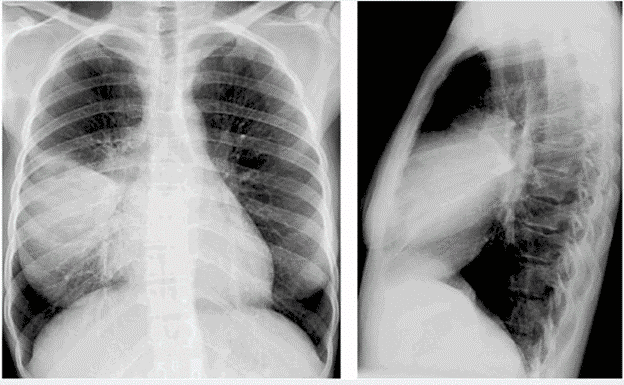

Phòng khám Đa khoa Hương Sơn trang bị hệ thống X-quang kỹ thuật số hiện đại, cho phép chẩn đoán nhanh và chính xác các bệnh lý về phổi, giúp người bệnh được can thiệp kịp thời và hiệu quả.

Phát hiện bệnh lý phổi phổ biến: Viêm phổi, lao phổi, tràn dịch màng phổi, u phổi, giãn phế nang, xơ phổi, khí phế thũng, COPD (bệnh phổi tắc nghẽn mạn tính)…

Hình ảnh rõ nét, độ phân giải cao: Cho phép quan sát chi tiết tổn thương nhu mô phổi, các vùng mờ, tổn thương dạng nốt, hang lao…